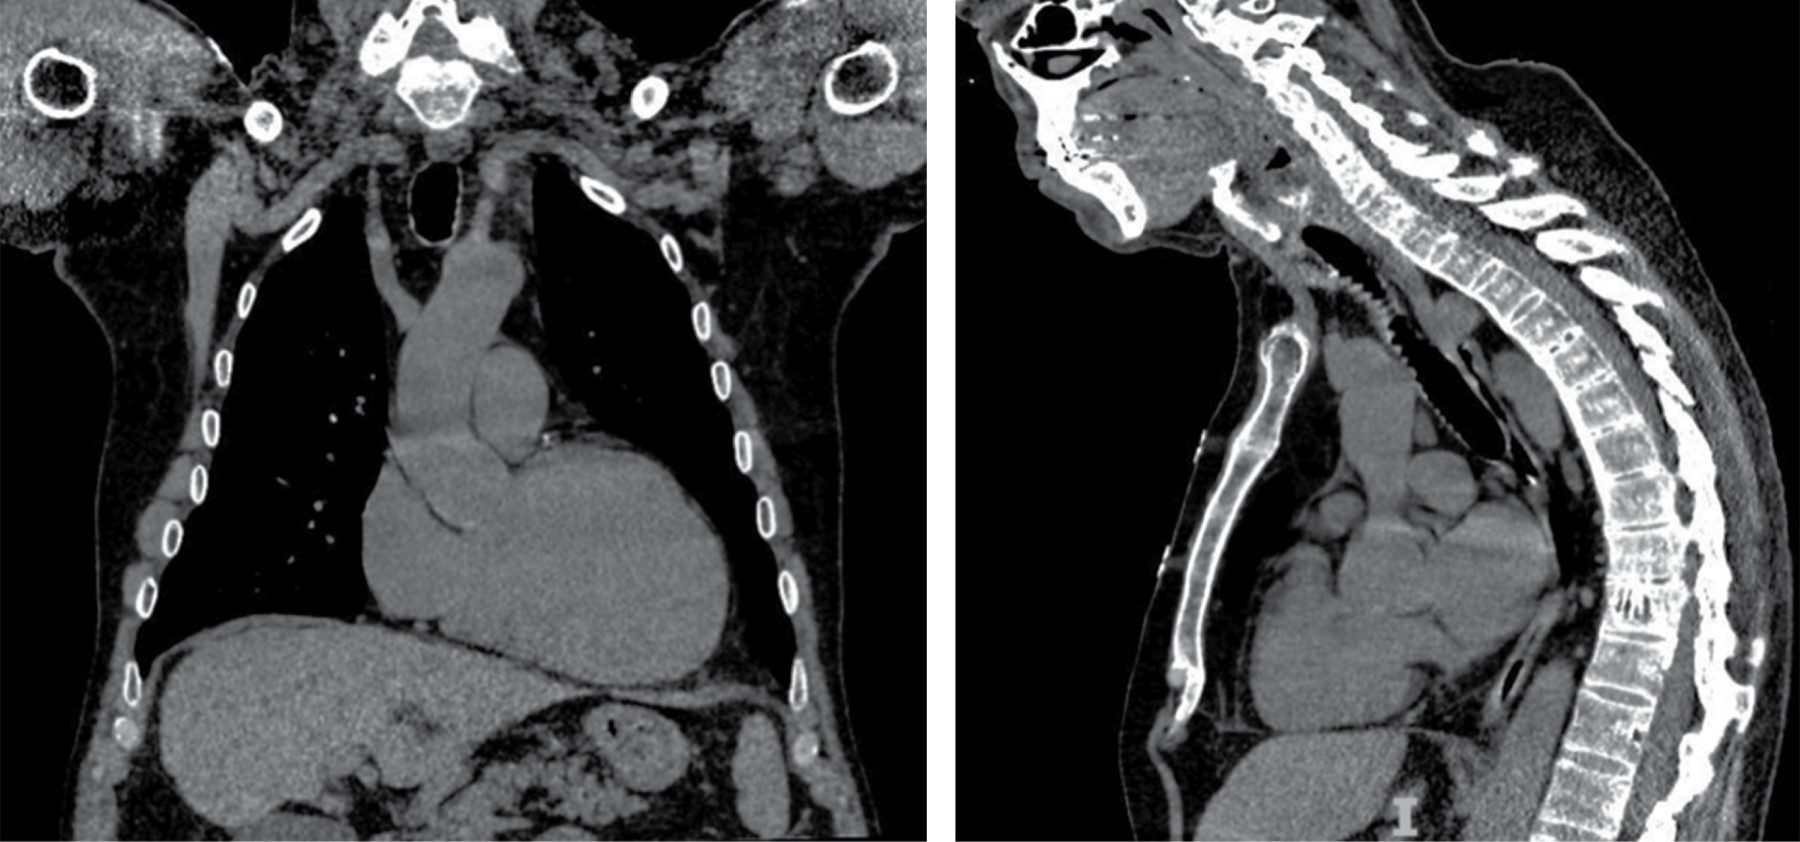

Figura 2